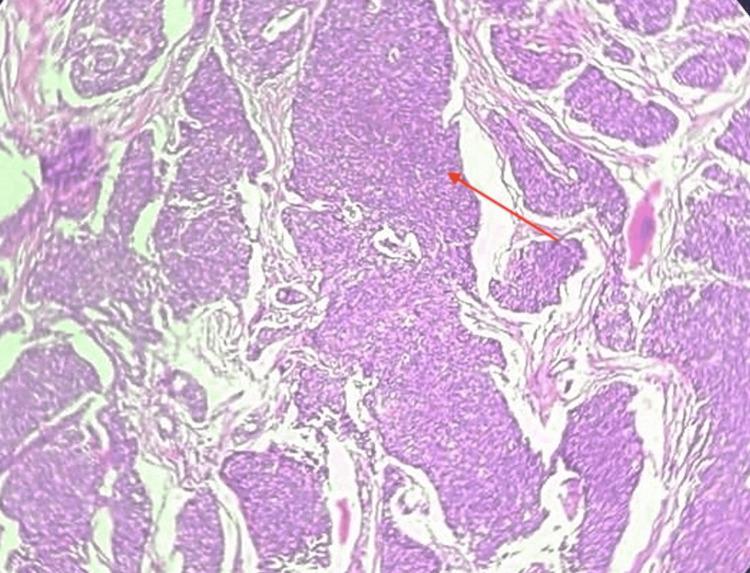

The incidence of mixed thyroid carcinoma of poorly differentiated thyroid carcinoma (PDTC) and papillary carcinoma thyroid is very unusual. PDTC exhibits a high degree of dedifferentiation and histopathological confirmation is done based on Turin's criteria. This type of carcinoma has a poor prognosis and the survival rates at five and ten years post-diagnosis are significantly lower compared to well-differentiated thyroid carcinomas. Surgery is the best mode of treatment at present. This is a case of a 71-year-old female who underwent total thyroidectomy with modified radical neck dissection which yielded a histopathological variant comprising PDTC and papillary thyroid carcinoma. The patient was followed up with a serial thyroglobulin antibody test and ultrasound of the neck at six months and one year, and both were found to be normal.

摘要

低分化甲状腺癌(PDTC)与甲状腺乳头状癌混合性甲状腺癌的发病率非常罕见。PDTC表现出高度的去分化,组织病理学诊断依据都灵标准进行。这种类型的癌预后较差,与高分化甲状腺癌相比,诊断后5年和10年的生存率显著降低。目前手术是最佳治疗方式。这是一例71岁女性患者,接受了全甲状腺切除术及改良根治性颈清扫术,术后病理结果为PDTC与甲状腺乳头状癌的组织病理学变异型。对该患者在术后6个月和1年进行了系列甲状腺球蛋白抗体检测及颈部超声检查进行随访,结果均正常。